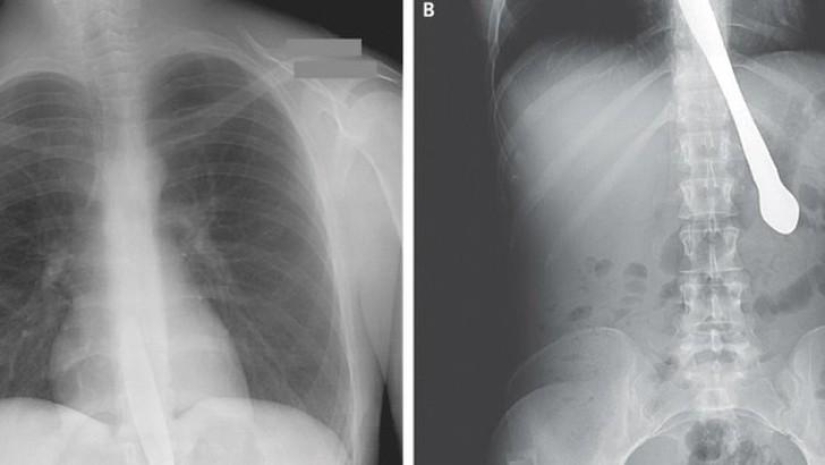

Scissors.